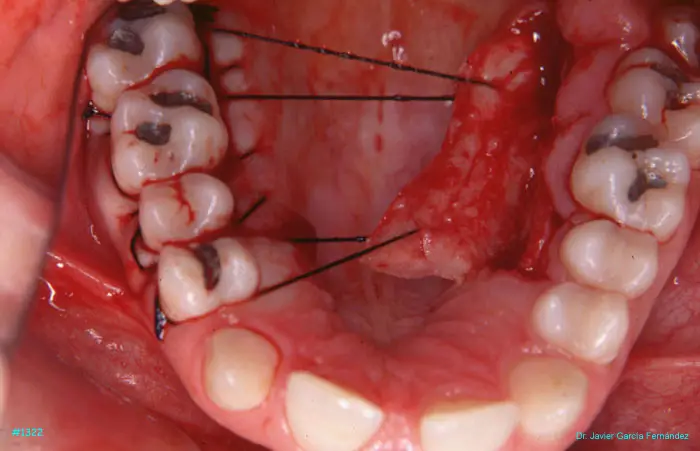

Atlas of Surgical Techniques in Periodontics. Chapter III. Atlas de Técnicas Quirúrgicas en Periodoncia